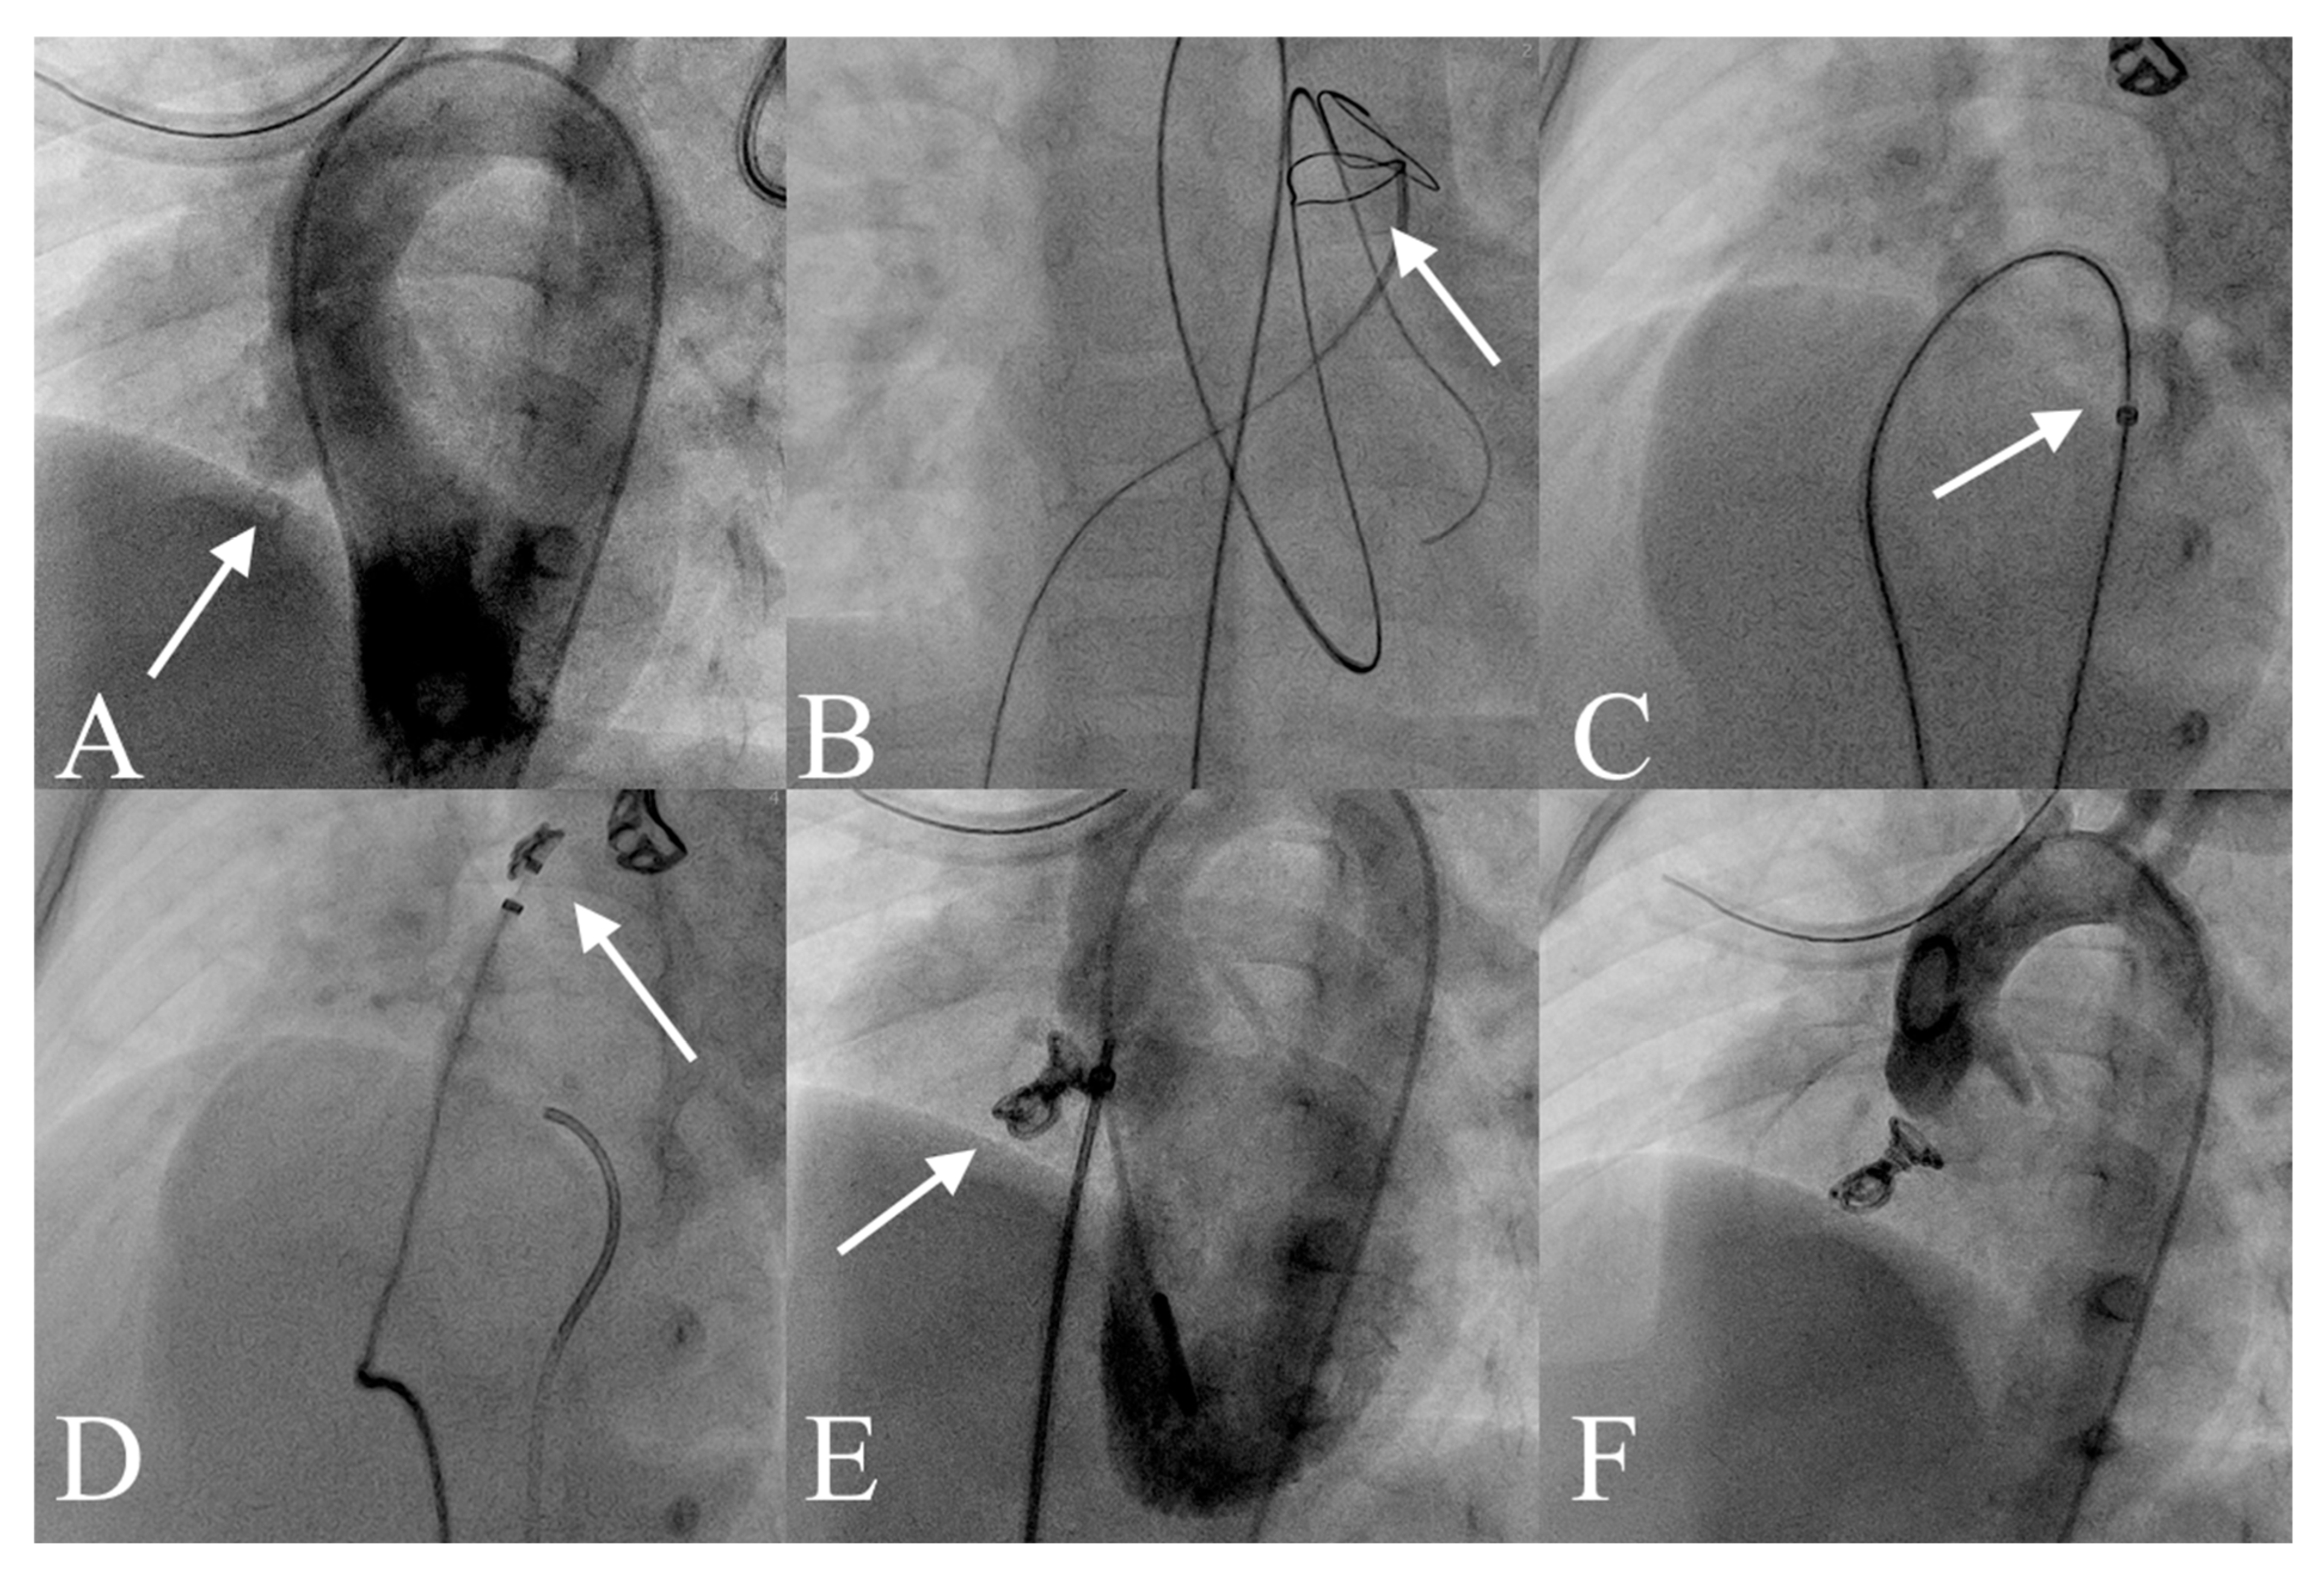

The transcatheter pmVSD closure procedures were conducted in the catheterisation laboratory under both echocardiographic and fluoroscopic guidance by the same experienced team of operators. All patients underwent the procedure under general anaesthesia. Under ultrasound guidance, the common femoral artery and vein were cannulated using 4F and 5F sheaths, respectively, followed by intravenous administration of heparin at a dose of 75–80 IU/kg. Left ventricular angiography was performed in the left anterior oblique (LAO) view with cranial angulation (LAO 50°, CRA 30°) to assess the size and morphology of the pmVSD (Figure 1A).

Transcatheter pmVSD Closure with the Nit-Occlud® Le VSD Coil. (A) Left ventricular angiography showing a pmVSD with aneurysmal tissue (white arrow). (B) A guidewire advanced through the defect from the left ventricle to the right ventricle and into the left pulmonary artery, forming an arteriovenous loop (white arrow). (C) The delivery catheter (white arrow) was advanced via venous access into the descending aorta, and the occluder was introduced through the catheter. (D) Formation of distal loops (white arrow). (E) Left ventricular angiography confirms appropriate device position (white arrow) with minimal residual shunt through the defect. (F) Final device position after release, with no evidence of aortic regurgitation. Abbreviations: pmVSD, perimembranous ventricular septal defect.

Device selection was guided by angiographic measurements, with the distal diameter of the coil chosen to be at least twice the effective diameter of the VSD on the right ventricular side and approximately 1–2 mm larger than the diameter measured from the left ventricular side [18]. After the evaluation, the defect was crossed retrogradely from the left ventricle using a 4F Berenstein catheter and a floppy hydrophilic wire. The wire was then snared on the right side, typically within the pulmonary artery, to establish an arteriovenous (a-v) loop (Figure 1B). The delivery sheath was introduced via the venous access and advanced over the wire across the VSD into the ascending aorta (Figure 1C). The Nit-Occlud® Lê VSD Coil was delivered through the sheath into the ascending aorta, where the distal loops were formed (Figure 1D). Except for the final two loops, all other loops of the coil were deployed in the ascending aorta. Gentle retraction of the system allowed it to cross the aortic valve and position the device across the defect (Figure 1E,F). When the coil was pulled back into the VSD, it typically conformed to the shape of the defect, assuming a conical configuration. Once the deployed loops were securely anchored within the VSD, the remaining two loops were positioned on the right ventricular side of the defect. For type C defects, the device was placed within the aneurysmal tissue to prevent protrusion into the left ventricular outflow tract. In patients without aneurysmal tissue, the coil ends were positioned on the left and right sides of the septum, respectively. The implantation was carried out utilising combined transthoracic echocardiography (TTE) and angiographic guidance.